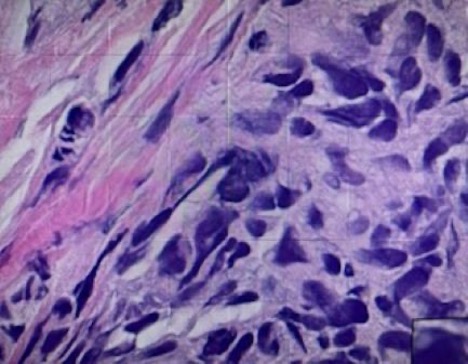

Treatment and Management. The lesion was excised in its entirety and sent for pathology (Fig. 1). Immunohistochemical stains showed tumor cells positive for S100, Sox10, and HMB45 and negative for pan-cytokeratin (AE1/AE3) supporting the diagnosis of malignant melanoma.

Fig. 1. Sections of the resected intranasal lesion reveal neoplastic cells with cytologic atypia, pleomorphism, and increased mitotic activity, consistent with malignant melanoma. Immunohistochemistry shows the tumor cells to be positive with HMB45, S100, and SOX 10, and negative for AEL/AE3 confirming the diagnosis of melanoma.